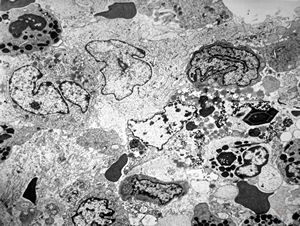

F,16y. | bone marrow -malignant histiocytosis

F,16y. | bone marrow - malignant histiocytosis